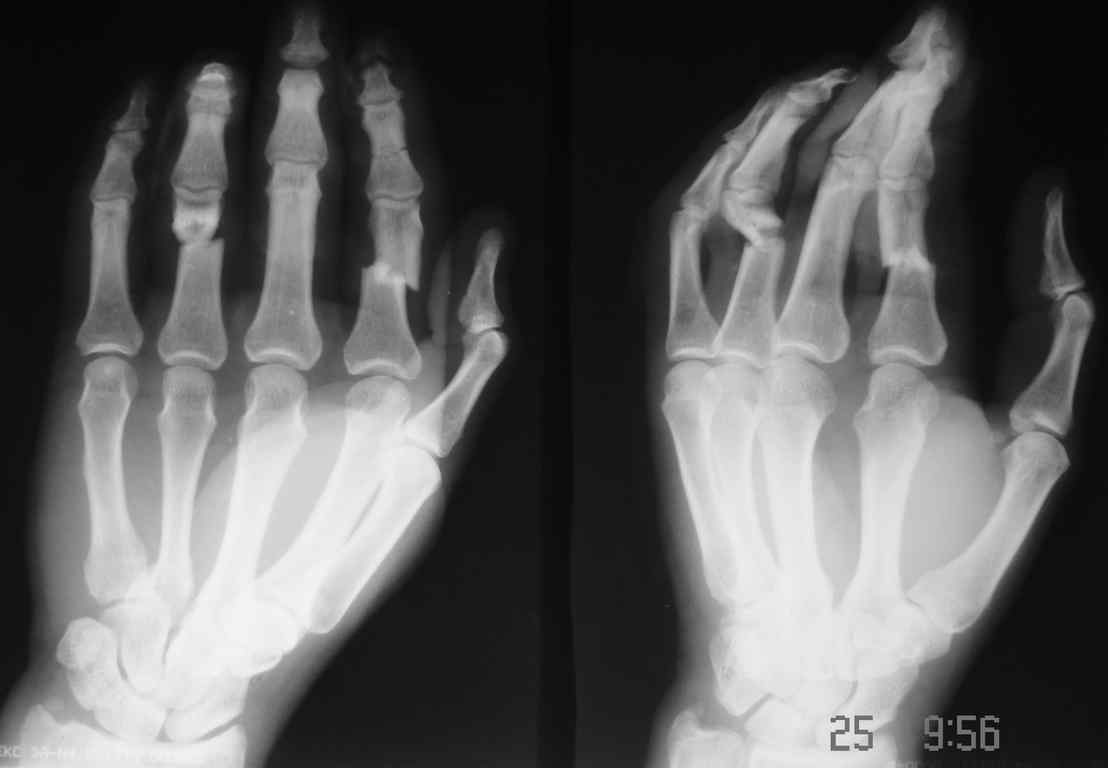

Обратился больной с контрактурой 2-4 пальцев кисти. Травма год назад - рука попала в шнек. Планируется оперативное лечение. Имеет-ли кто опыт укорачивающих остеотомий фаланг пальцев в подобных случаях?